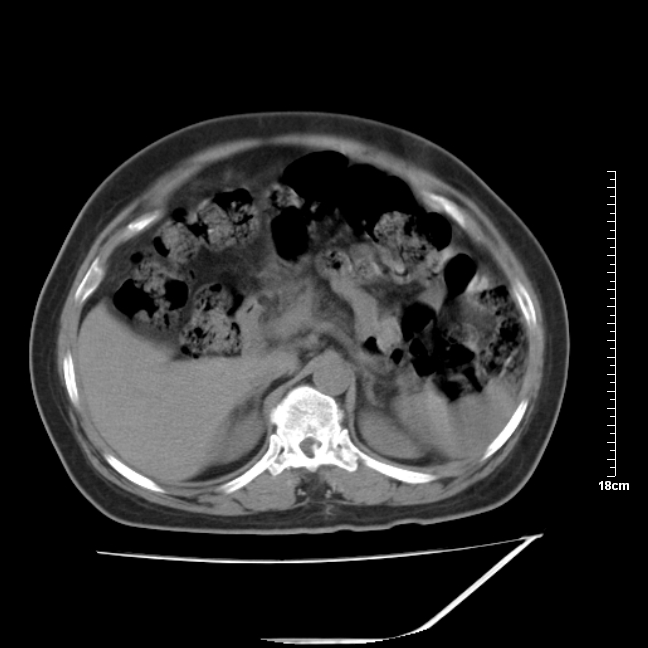

以下是引用jinning在2007-5-17 11:18:00的发言:[br]考虑右侧卵巢囊腺瘤合并少量出血可能性大